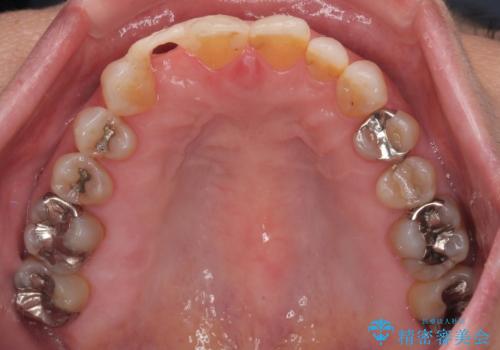

仮歯を事前に用意し、インプラント埋入時に即日で仮歯を装着する、即時荷重インプラントの計画で治療を進めて行くこととしました。

新幹線や飛行機を利用しても来院であり、極力来院回数を減らしたり、東京に用事があるタイミングに合わせてアポイントを調整したりと、負担が少なくなるようにして治療を進めて行きました。

来院間隔があいたため、予定よりも長くなりましたが、大きなトラブルもなく、外科処置は1回のみ、最小の来院数で無事に治療を終えることができました。